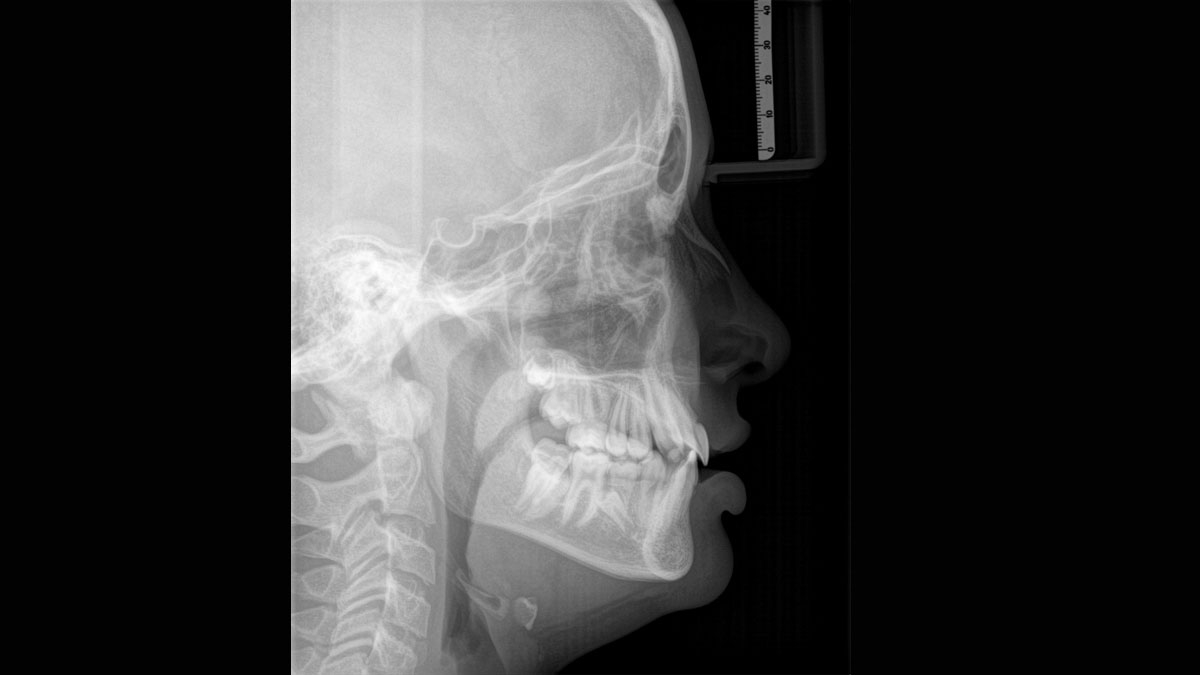

We developed a 10-point concept for easy patient positioning and X-ray imaging. Our concept is primarily about two things: high image quality and comfort for the patient and the assistant. This concept supports and provides the tools needed to ensure high-quality images for treatment analysis and focuses on ergonomics and comfort for the patient and assistant. The patented bite block technology, for example, automatically establishes the correct inclination of the patient's head, positioning the patient in the occlusal plane, partnering with the 3 point head fixation and firm handles to ensure stable positioning-limiting unnecessary correction scans.